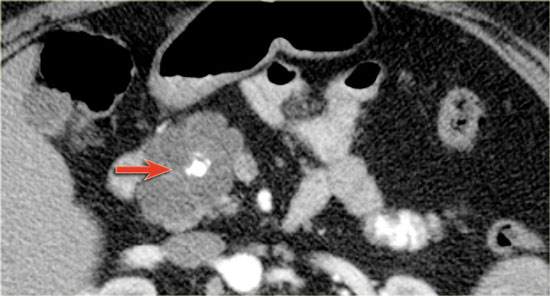

CT-images of an IPMN with a dilated pancreatic duct (blue arrows).

Notice enhancing solid nodule in the pancreatic head (red arrow).

Continue with the ultrasound-image.

The US-image shows a large branch-duct component within the pancreatic head.